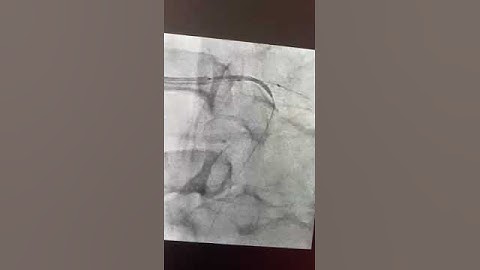

Deficult scenario during p pci. culprit LCX. non Culprit LMS and LAD.